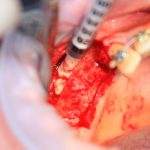

Изоляция области аутографта и имплантатов барьерной мембраной.

Перекрывать костный блок барьерной мембраной или оставить так? По этому вопросу есть много мнений. Между тем, в публикации по методике есть ясное показание, когда это требуется.

Конкретно в этом клиническом случае между костным аутотрансплантатом, ложем и имплантатами есть пустое пространство. Если его не изолировать от мягких тканей, они прорастут и осложнят интеграцию аутографта. Поэтому я решил перекрыть костный блок барьерной мембраной, пусть это делает хирургическую операцию немного дороже.

— я использовал барьерную мембрану Geistlich Bio-Gide, которая имеет две разные поверхности: с одной стороны она рыхлая «адгезивная», с другой — гладкая и прочная. Как укладывать — на результат не влияет, но в плане удобства рыхлую поверхность мы «приклеиваем» к тому, на чем требуется барьерную мембрану удержать. В данном случае хотелось бы удержать её на костной поверхности — следовательно, мы укладываем её рыхлой поверхностью к кости.

— много лет мы используем антибиотики для интраоперационной профилактики инфекционно-воспалительных осложнений. Уже в то время мы пришли к выводу, что удобнее всего — порошки антибактериальных препаратов для приготовления раствором: дешевые, стерильные, в удобной упаковке. Прямо в виде порошка их можно добавлять в графт, растворы для ирригации, либо использовать так, как показано на фото. Еще мы используем порошок антибиотика для изготовления пасты, которой обрабатываем имплантаты в процессе ревизии или при лечении периимплантита. Это удобнее и эффективнее, чем интраоперационное использование жидких форм антибактериальных препаратов.

— ты знаешь, что барьерная мембрана может выполнять две функции, каркасную и изолирующую. Первая функция требует обязательной фиксации и натяжения, вторая — нет. В нашем случае «каркасом» регенерата является костный блок, а барьерная мембрана нужна только для изоляции. Поэтому она не требует натяжения и фиксации пинами.

После я внимательно проверил, что костный блок и имплантаты полностью перекрыты. Теперь рану можно ушивать.